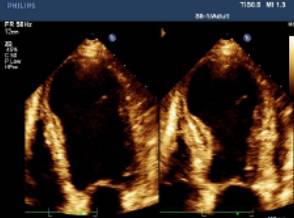

以下图片显示了主动脉瓣反流束的宽度与左室流出道的宽度的比例以及射流紧缩口宽度测量方法。